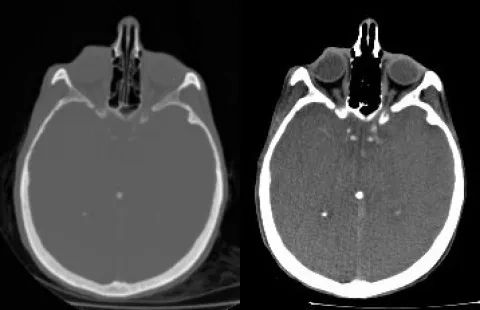

Ilustrácia k heslu kontrast

Snímka ľudskej hlavy vytvorená počítačovým tomografom. Kosť je svetlá, mäkké tkanivá sú sivé. Vľavo je neupravená snímka, vpravo kontrast upravený na skúmanie mäkkých tkanív.

Snímka ľudskej hlavy vytvorená počítačovým tomografom